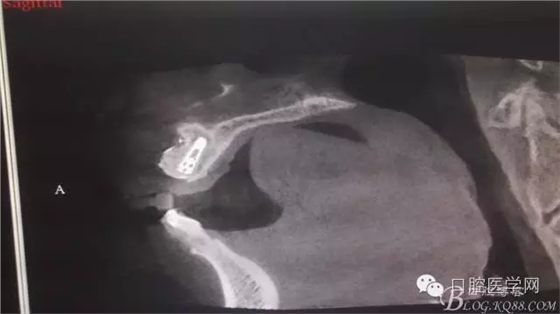

植入種植體左側(cè)3510,右側(cè)4010,植骨Bioss,蓋膜Cytoplast。骨膜減張垂直褥式縫合加間斷縫合。

之所以選擇Bioss是考慮其降解速度較慢,種植體接觸大面積為自體骨,Bioss可以很穩(wěn)定的緩慢吸收逐步引導(dǎo)骨再生。